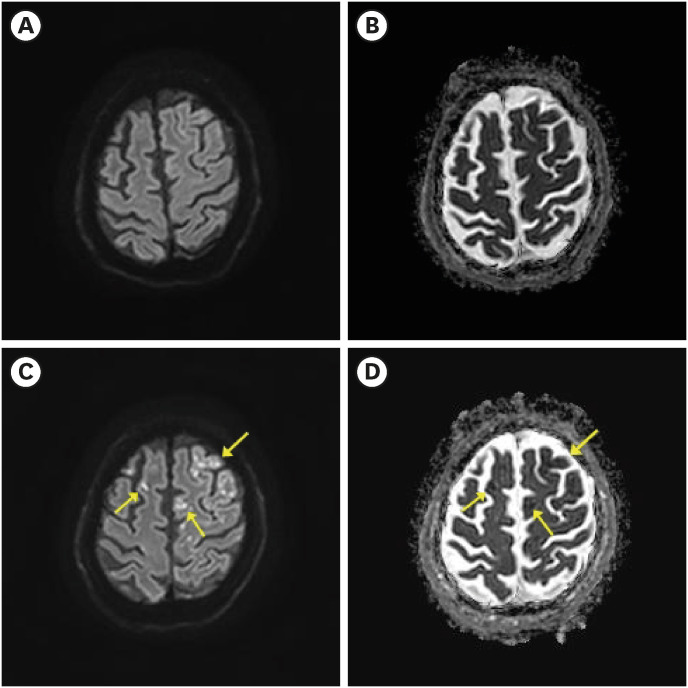

Cerebral air embolism (CAE) occurs in various clinical situations such as surgery, angiography, and hemodialysis; most are iatrogenic. Here we report the case of a 57-year-old man who developed CAE immediately after air-powder abrasive treatment, which is commonly used in dentistry. The patient underwent air-powder abrasive treatment for peri-implantitis, and immediately after the treatment, cardiac arrest occurred and cardio- pulmonary resuscitation was performed. After resuscitation, brain computed tomography performed in the emergency room showed scattered dark density presumed to be air. The day after admission, the patient showed right hemiplegia and a multifocal cerebral infarction was observed on brain magnetic resonance imaging. Therefore, CAE was strongly suspected. After hyperbaric oxygen treatment (HBOT), which started 4 days after the incident, the patient regained consciousness and showed improvement in cognitive impairment, and only grade 4 muscle weakness was observed in the right lower extremity on the manual muscle test. This case highlights the importance of considering CAE as a possible cause of neurological symptoms occurring during clinical procedures involving air, and adds to the accumulation of evidence of therapeutic effects of delayed HBOT.